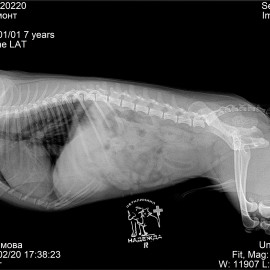

Наш пациент собака породы цвергпинчер по кличке Вальмонт.

Обратились с жалобами на нарушение опороспособности на задние лапы.

После проведённых неврологических тестов и рентгенологического исследования был поставлен предварительный диагноз: болезнь межпозвонкового диска. Было назначено проведение магнитно-резонансной томографии, после которой был поставлен точный диагноз: экструзия межпозвонкового диска на уровне TH12 - TH13 (12 -13 позвонков грудного отдела).

Была проведена операция: левосторонняя гемиламинэктомия на уровне TH12 - TH13.

Снимки во время исследования пациента.